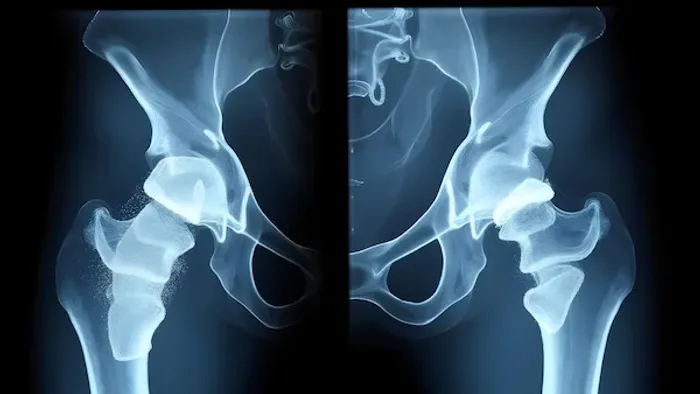

Over time, the bond between the implant and your natural bone can weaken. This is the leading reason for hip revision surgery. The cement can degrade, or the bone may fail to grow into a cementless implant properly. This loosening causes pain, especially when you start moving after a period of rest, and a feeling of instability. It's often confirmed through X-rays that show a gap between the implant and the bone.

As the plastic liner of the hip socket wears down, it releases tiny particles. In some patients, the body's immune system reacts to these particles by attacking the surrounding bone tissue, causing it to deteriorate. This process, called osteolysis, can lead to significant bone loss, making the implant loose and potentially causing a fracture. Revision surgery allows the surgeon to clean out this debris and rebuild the bone structure.